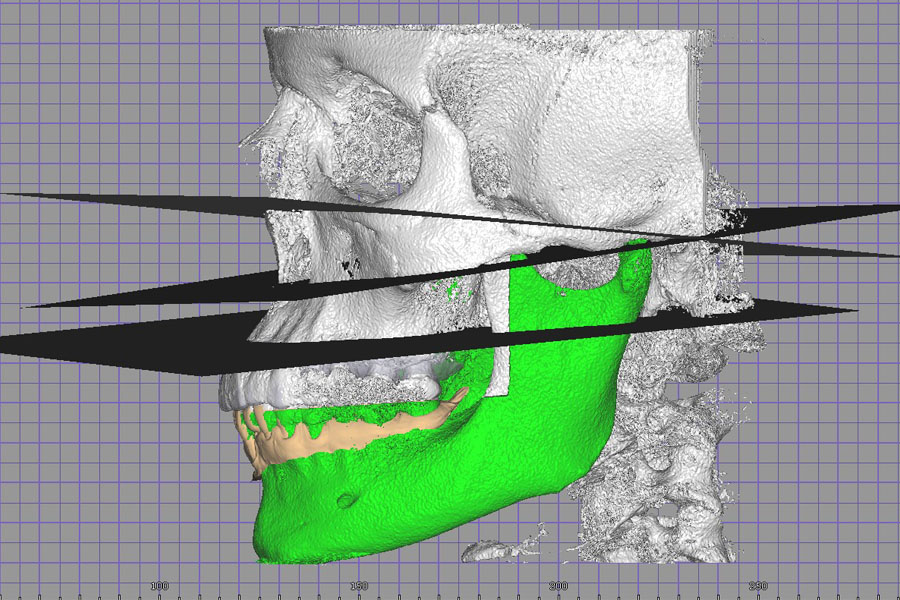

Allows you to work with dynamic data, virtual models, and CBCT data. You can visualize occlusal contacts and all dynamic abnormalities. Using CBCT data, you can determine the bite height and identify joint dysfunctions. You get a virtual patient.

Record axiography, make face and tooth scans, import CBCT

Merge all data into one 3D model. See all in real-time animation

Set new jaw place, calculate future position of a jaw. AI will assist you with it